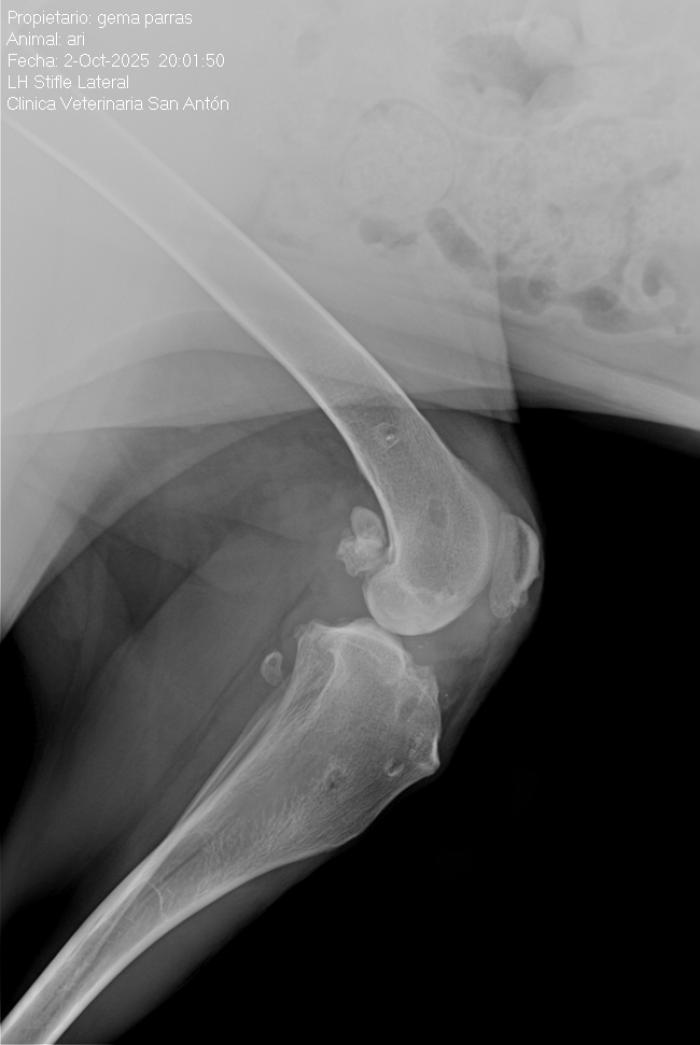

El ligamento de polietileno ultrarresistente de ultra alto peso molecular, se fija mediante tornillos interferenciales de titanio (Figura 2).

- la isometría: colocación de los puntos isométricos,

- las fibras libres: posicionamiento de las fibras libres (Figura 3),

- la tensión a ejercer: regular la tensión que ejerce ese ligamento.

- Llega otro caso que después de 5 años con buena condición del animal , debuta con una fístula, que posiblemente requiera retirada de implante (Figuras 11-13).